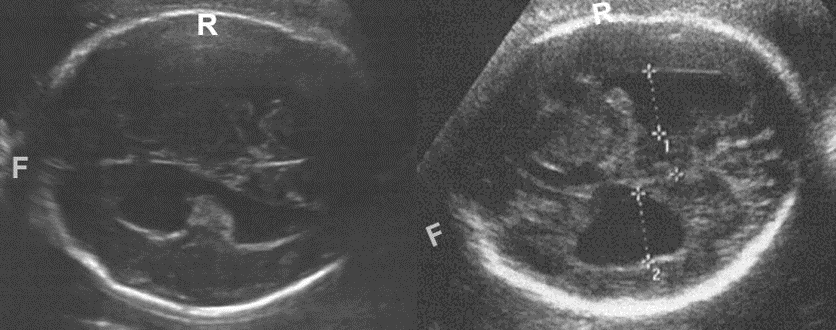

Heterozygous pathogenic COL4A1/2 variants cause early-onset cerebrovascular diseases, including porencephaly and schizencephaly. Although most of them are developed during prenatal periods, little had been known about their prenatal clinical features. We identified 56 individuals with pathogenic COL4A1/2 variants, and obtained prenatal clinical information in 47 individuals. Only about 30% of them exhibited prenatal findings that were strongly suggestive of features associated with COL4A1/2 variants. In contrast, non-specific findings such as ventriculomegaly (shown in photos) and fetal growth restriction were the major prenatal initial signs of COL4A1/2-related disorders. Our work extends the prenatal phenotypic varieties of COL4A1/2-related disorders, and it would be valuable for the consideration of the prenatal genetic diagnosis of COL4A1/2-related disorders. (By Dr. Satoko Miyatake, https://jmg.bmj.com/content/early/2020/07/30/jmedgenet-2020-106896 )

Deformed ventriculomegaly are prenatally seen in two patients at 34 (left) and 30 (right) weeks of gestation.